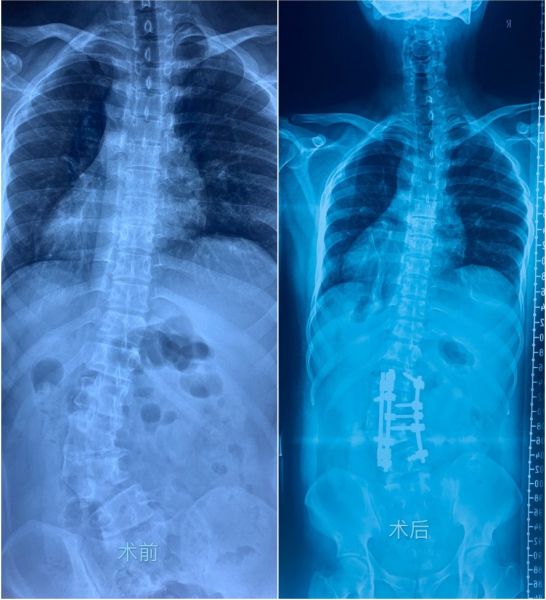

手术前后患者脊柱X光片对比

20岁的临沂小伙王某学生时代就有腰背部不平且躯干向一侧倾斜的情况,一年多前出现腰背部酸痛不适,逐渐加重并出现左下肢麻痛无力。王某慕名到烟台山医院脊柱外二科就诊,三维CT清晰显示其第3节腰椎呈楔形“嵌在”脊柱中间,导致整个脊梁向右侧“C”型弯曲达50度,严重扭转的脊柱为手术增加了难度及神经损伤的风险。脊柱外二科主任吕世桥带领团队详细测量各项影像学参数,多次集体讨论,选取最佳方案,以最大程度保证手术成功。

手术由脊柱外二科王静杰副主任医师主刀,在麻醉科、手术室及神经监测团队的默契配合下,经过8个小时专业熟练的操作,手术顺利完成。

术后48小时王某即离床活动,小伙子个子长高了,腰杆直了,下肢麻痛感也消失了,再三表示感谢烟台山医院脊柱外二科团队帮自己挺直了脊梁。